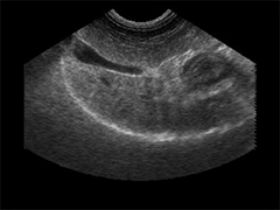

עוד עובר מקסים בן 6 שבועות